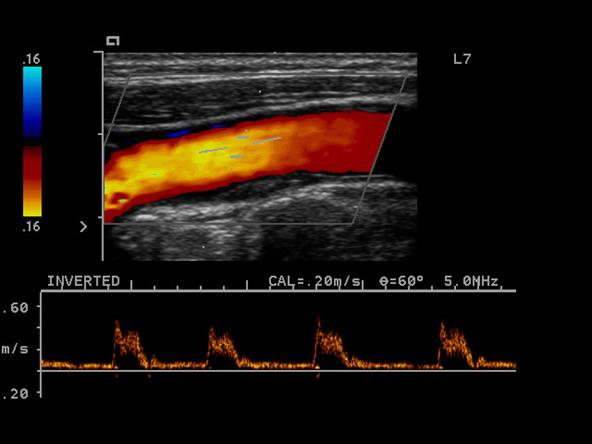

Explain the waveform of the CCA

Mimics both ICA and ECA waveforms

Explain the waveform of the ICA

low resistant - constant forward flow

Forward flow throughout the cardiac cycle

Explain the waveform of the ECA

high resistant

steep forward stroke

Forward flow during systole, low or reverse diastolic component

Explain the waveform of the vertebral artery

low resistant

Where is peak systole?

The highest point on the wave form

Where is end diastole?

The point just prior to the systolic upstroke